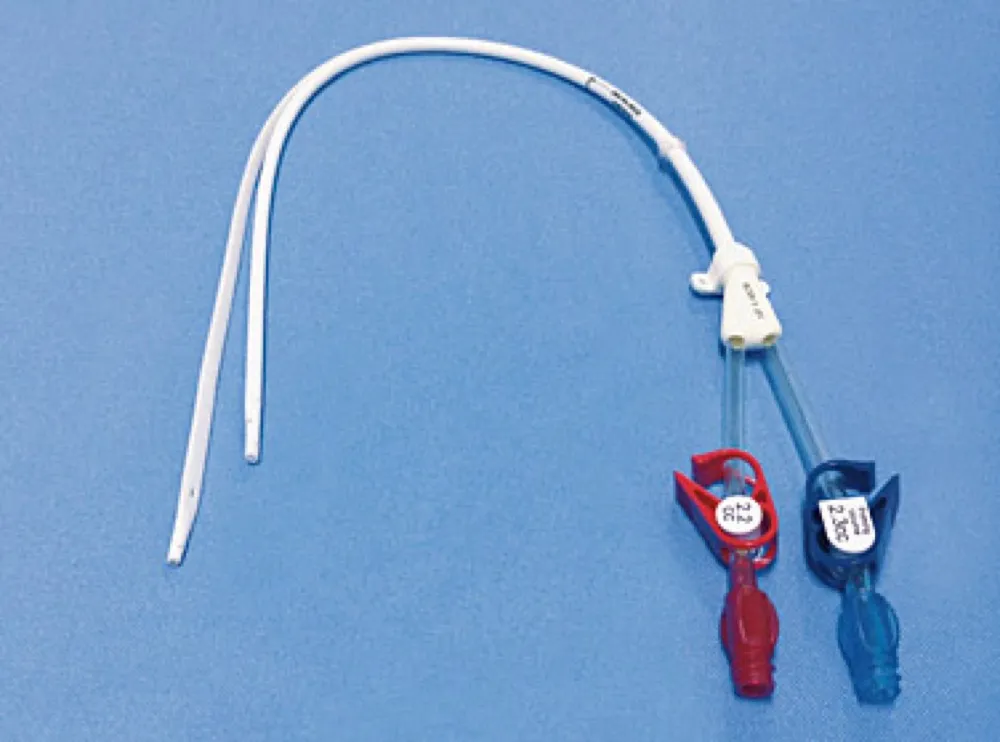

Particularidades da IRA e diálise no paciente cirrótico

Particularidades da IRA e diálise no paciente cirrótico